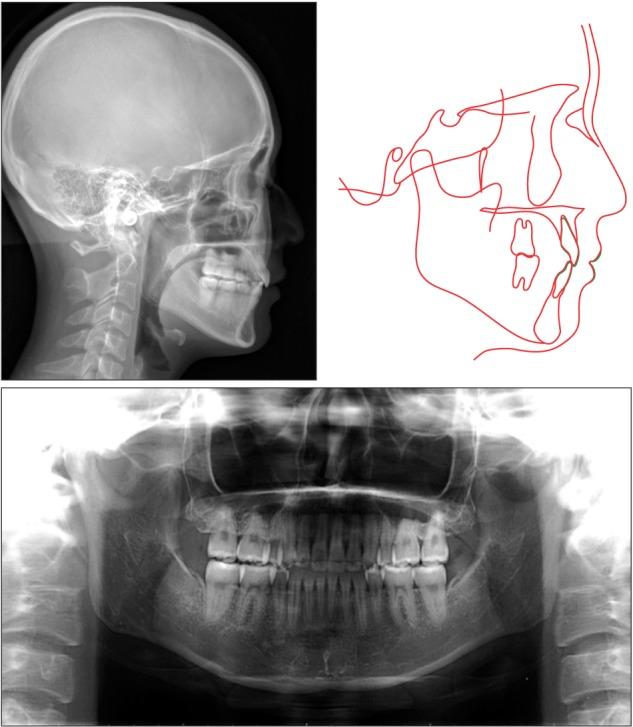

For patients with bimaxillary protrusion, significant retraction and intrusion of the anterior teeth are sometimes essential to improve the facial profile. However, severe root resorption of the maxillary incisors occasionally occurs after treatment because of various factors. For instance, it has been reported that approximation or invasion of the incisive canal by the anterior tooth roots during retraction may cause apical root damage. Thus, determination of the position of the maxillary incisors is key for orthodontic diagnosis and treatment planning in such cases. Cone-beam computed tomography (CBCT) may be useful for simulating the post-treatment position of the maxillary incisors and surrounding structures in order to ensure safe teeth movement. Here, we present a case of Class II malocclusion with bimaxillary protrusion, wherein apical root damage due to treatment was minimized by pretreatment evaluation of the anatomical structures and simulation of the maxillary central incisor movement using CBCT. Considerable retraction and intrusion of the maxillary incisors, which resulted in a significant improvement in the facial profile and smile, were achieved without severe root resorption. Our findings suggest that CBCT-based diagnosis and treatment simulation may facilitate safe and dynamic orthodontic tooth movement, particularly in patients requiring maximum anterior tooth retraction.

对于双颌前突患者,有时显著内收和压低前牙对于改善面部外形至关重要。然而,由于多种因素,治疗后上颌切牙偶尔会出现严重的牙根吸收。例如,有报道称,内收过程中前牙根尖接近或侵入切牙管可能会导致根尖牙根损伤。因此,确定上颌切牙的位置是此类病例正畸诊断和治疗计划的关键。锥形束计算机断层扫描(CBCT)可能有助于模拟上颌切牙及周围结构的治疗后位置,以确保牙齿安全移动。在此,我们展示一例双颌前突的安氏II类错牙合病例,其中通过对解剖结构的预处理评估和使用CBCT模拟上颌中切牙移动,将治疗引起的根尖牙根损伤降至最低。在没有严重牙根吸收的情况下,实现了上颌切牙的大量内收和压低,从而显著改善了面部外形和笑容。我们的研究结果表明,基于CBCT的诊断和治疗模拟可能有助于实现安全、动态的正畸牙齿移动,特别是在需要最大程度内收前牙的患者中。